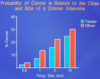

Is sporadic or familial colorectal cancer more common? 1o difference?

- Majority of cases SPORADIC (see attached image)

- Cumulative incidence much higher at younger ages in FAP, then HNPCC -> genetic syndromes, as compared with the general public